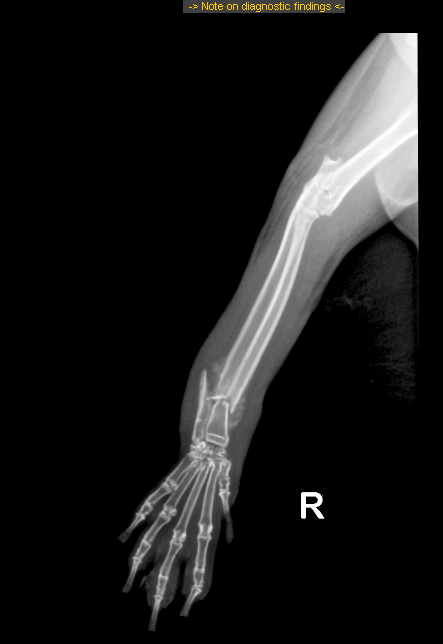

trzeba być #Kefirka.ą, żeby w ramach walki z usztywnieniem na łapie zrobić sobie przemieszczenie kości strzałkowej, do tego wygryźć w 2 miejscach futro do krwi. tydzień na hydroksyzynce ma zapisany

#Kefirka prawie zrosła sobie kość promieniową, natomiast kość łokciowa się nie zrasta. bo nie. na dodatek mamy w kości promieniowej martwiczak(a) (jaka forma jest prawidłowa). ale pogryziona własnozębnie łapka nie ma martwicy.